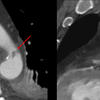

MAI x 2

Unusual location

Date: 08/14/2012

Views: 3183